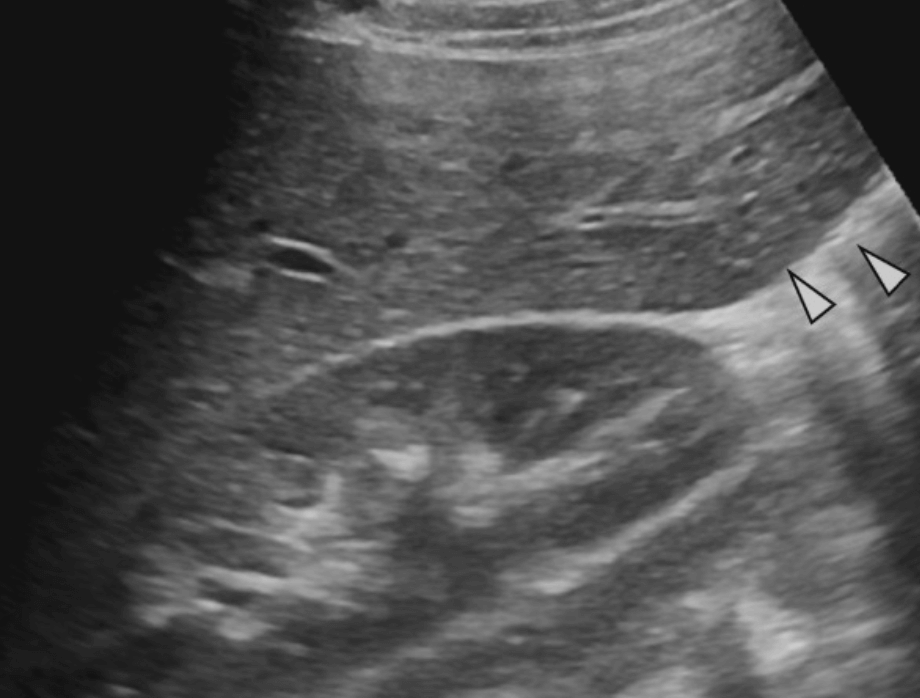

2. Long left lobe of the liver = Beaver tail liver

Beaver tail liver 좌엽이 길고 커져서 비장에 인접해 있다. 마치 비장의 피막하 혈종(subcapsular hematoma)처럼 보인다. 주로 마른 여자에서 확인된다.